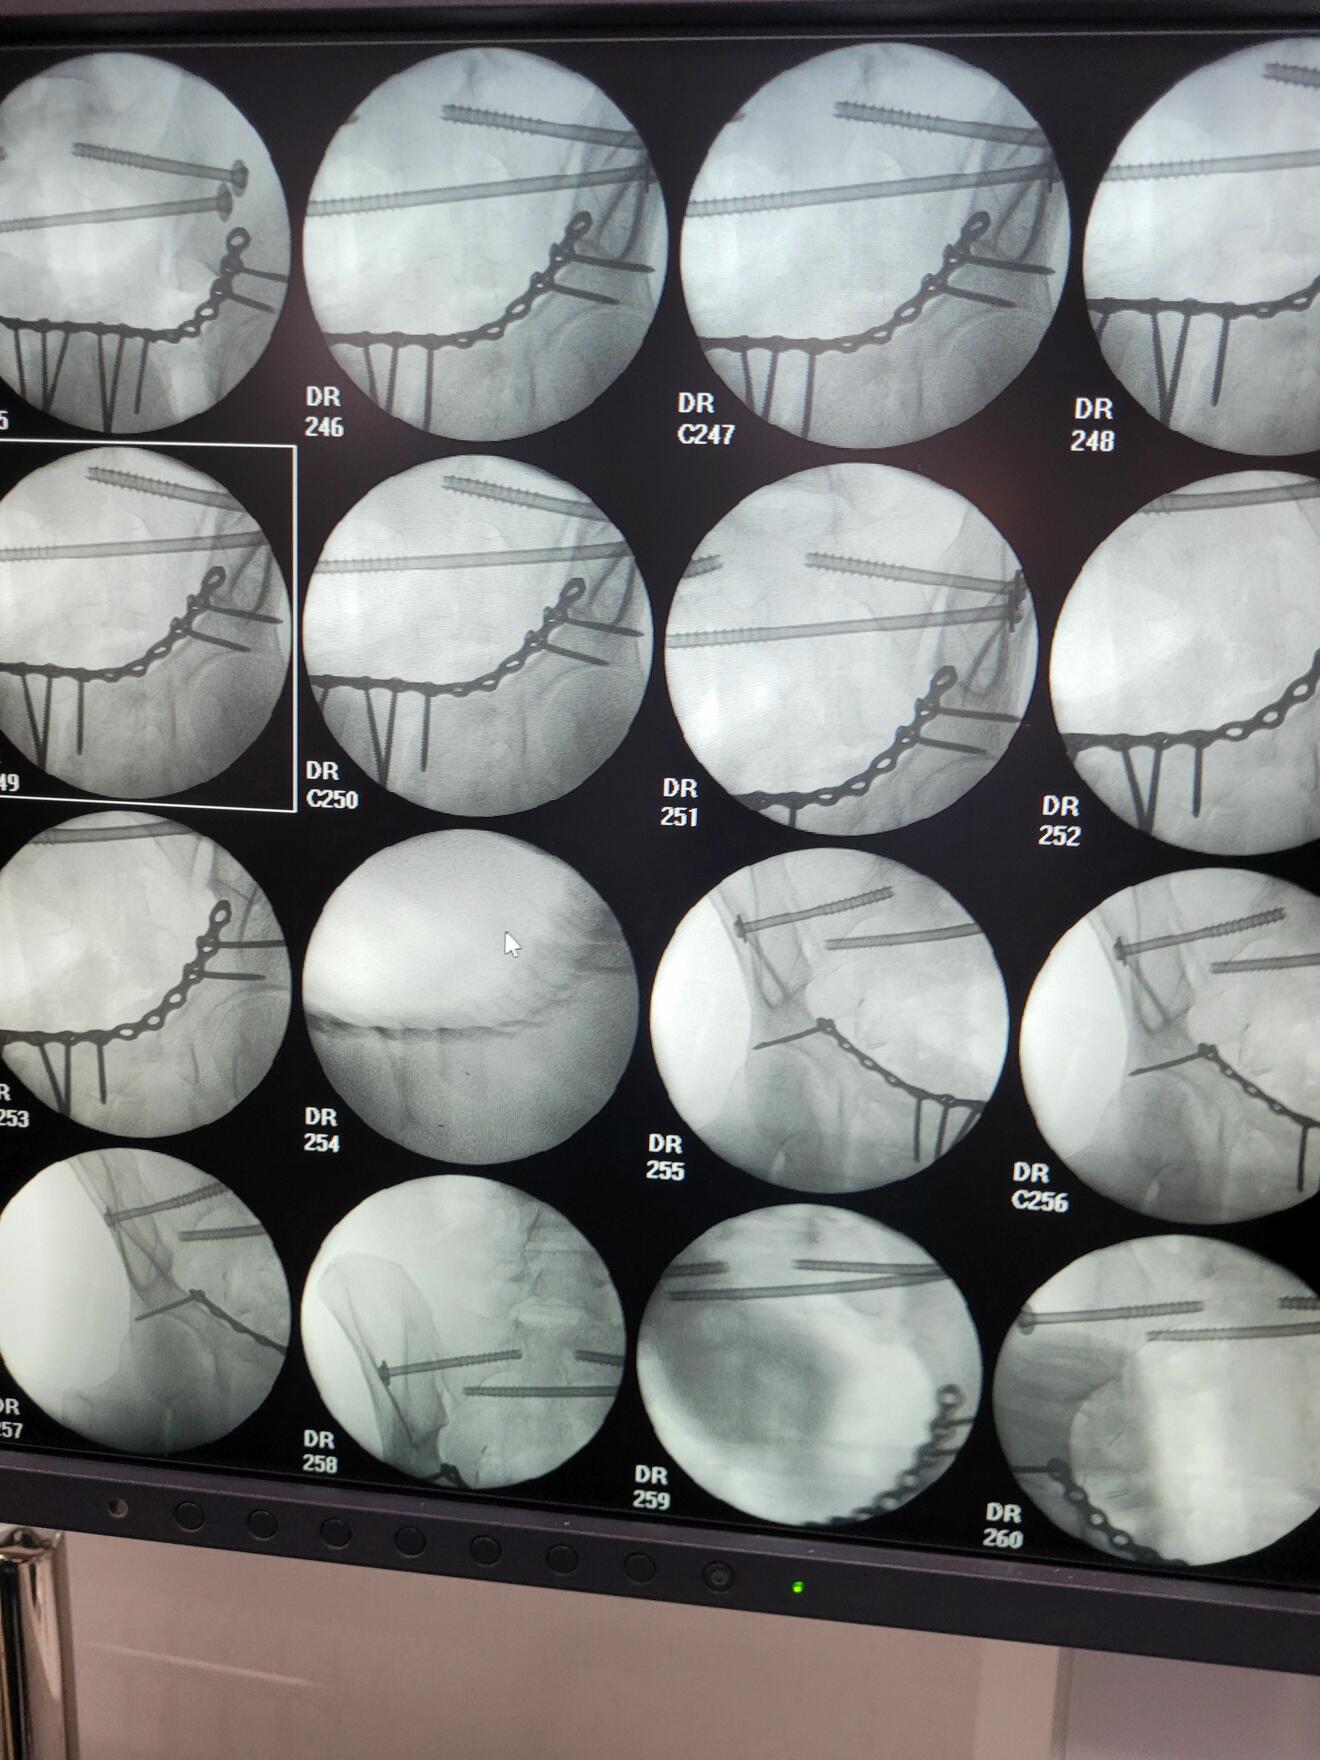

Moreover, the hospital's well-equipped trauma room, along with its comprehensive range of diagnostic and treatment options in the intensive care unit, allows for the effective treatment of polytraumatized patients. Severely injured patients with blunt abdominal trauma, traumatic brain injuries, and concomitant injuries to the pelvis and spine are treated here daily. I greatly appreciated the challenging and critical discussions on treatment strategies for these severely injured patients with the surgical colleagues on duty. It is not uncommon for patients with severely displaced fractures to be transferred after a delay in treatment, which can present additional challenges in surgical practice.